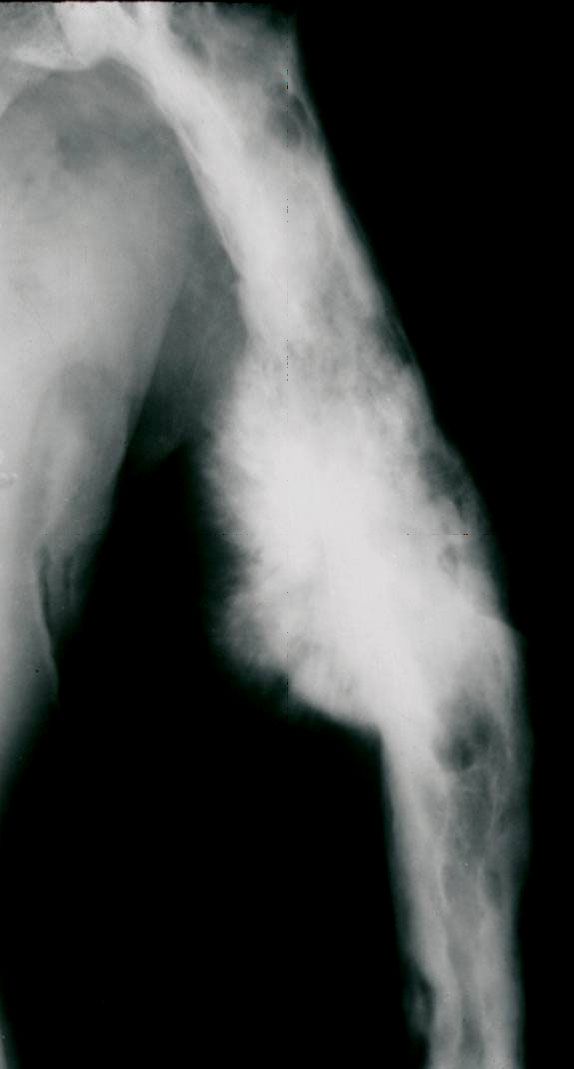

Paget's sarcoma

Paget's sarcoma of the humerus (upper arm bone). The tumors are very rare, but they are more likely to develop in older patients with long-standing Paget's disease.

Reproduced from Moon BS, Luna JT, Raymond KA, Madewell JE: Paget’s disease of bone. Orthopaedic Knowledge Online Journal 2010; 8(1). Accessed June 2017.